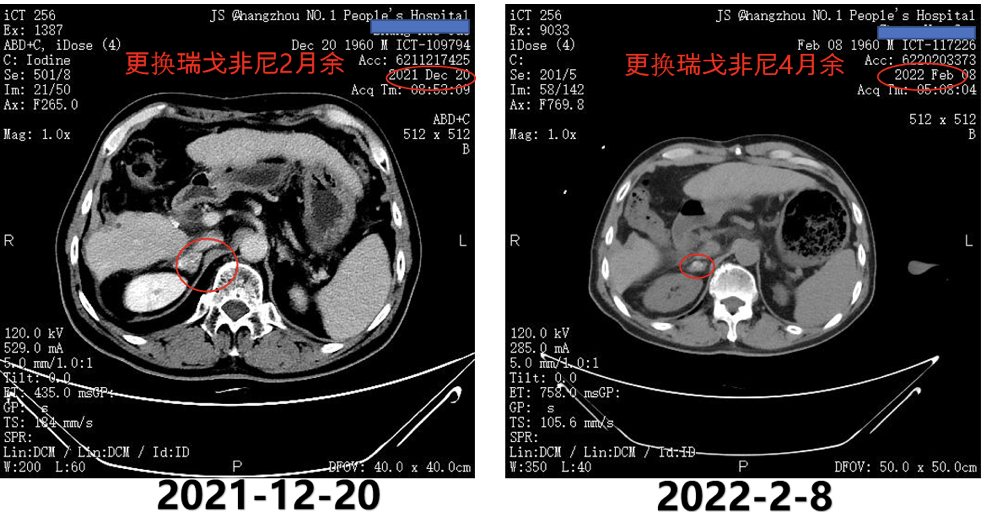

2021年12月20日复查CT示,右侧肾上腺病灶明显缩小,髂骨病灶也进一步缩小(图9)。

图9.2021年12月20日复查CT

2022年2月8日复查CT提示,肺部病灶基本消失(图11),肾上腺病灶明显缩小,髂骨病灶进一步退缩(图12)。2022年2月9日AFP为411ng/ml。

图12.2022年2月8日复查CT